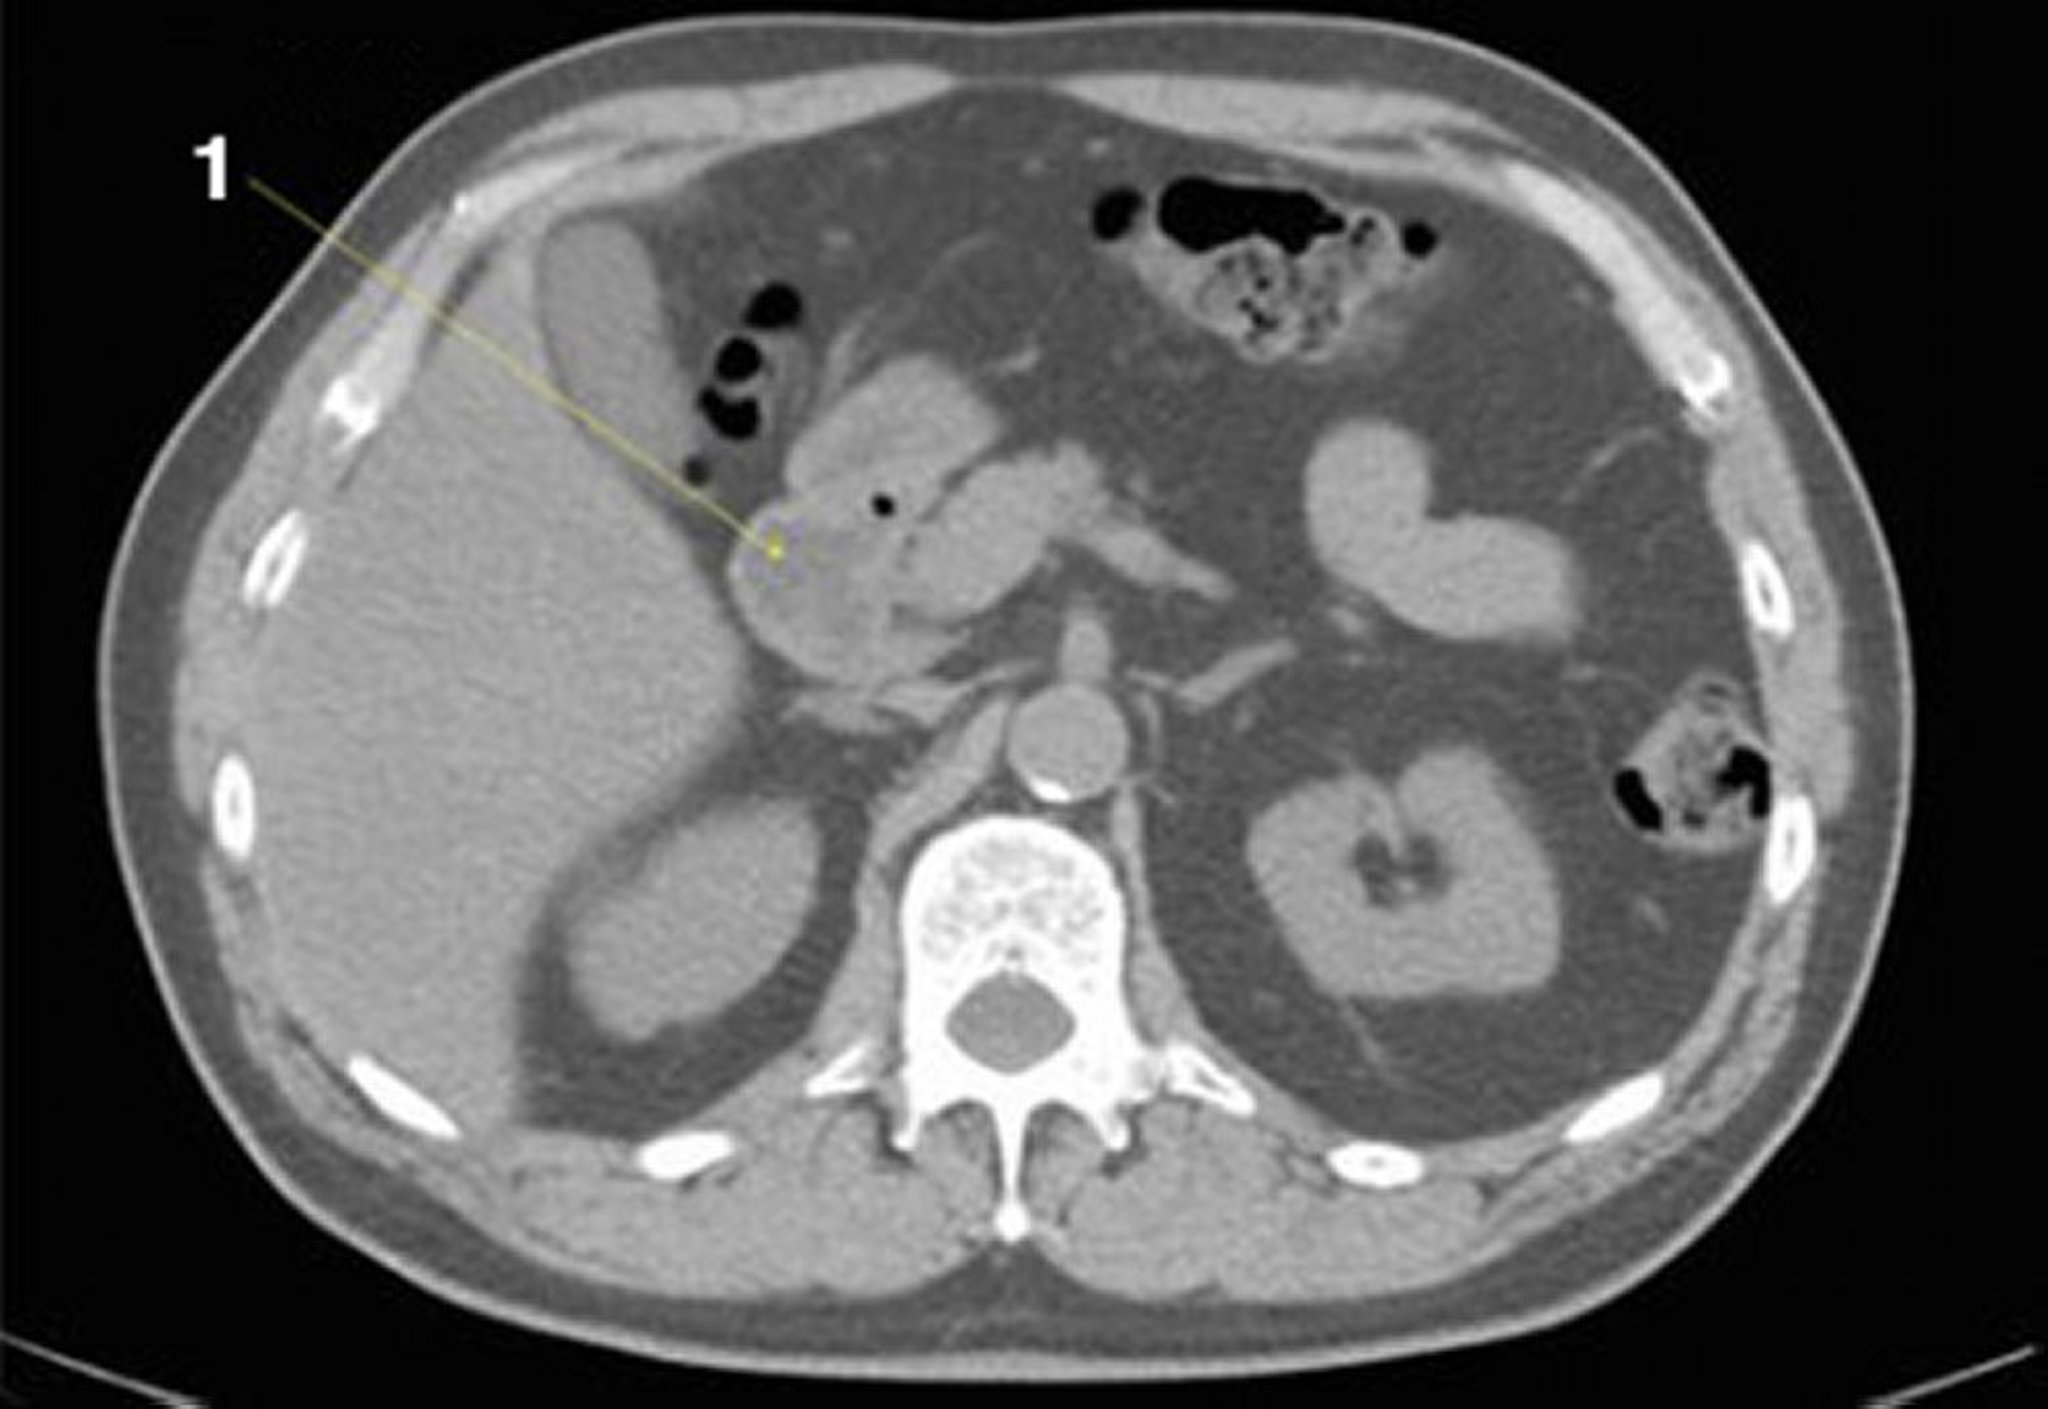

Phim chụp CT vùng bụng và vùng chậu không thuốc cản quang cho thấy giải phẫu bình thường (lát cắt 11)

1 = tá tràng.